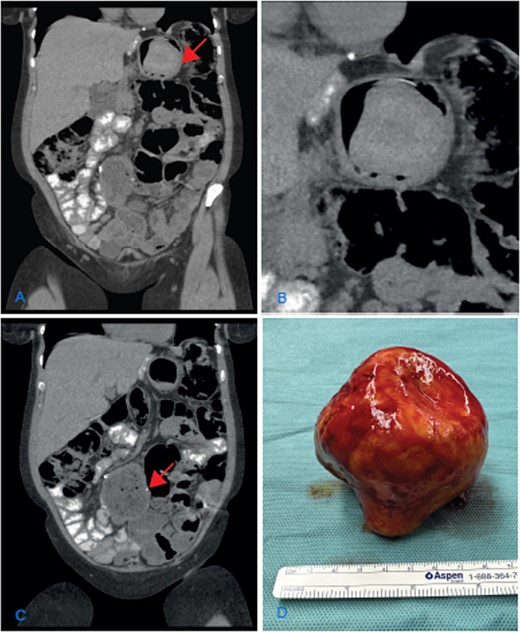

The clinical examination and lab results were normal. A gastroscopy did not reveal any pathological findings. The abdominal CT scan showed dilation of the jejuno-jejunostomy (JJ), biliopancreatic limb, and gastric remnant (Fig. 1A and C). Within the gastric remnant, hypodense mass of at least 5-cm diameter was detected (Fig. 1B). Considering the imaging findings, the patient was proposed for revisional surgery.

(A) Coronal CT scan image showing the dilatation of the gastric remnant with hypodensemass (arrow); (B) zoom of the gastric remnant with a 5-cm hypodense mass; (C) coronal CT scan image of the dilated JJ-anastomosis (arrow); (D) retrieved specimen a gallstone with approximately 10-cm diameter.